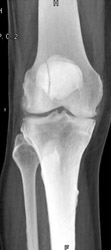

Scaphoid Fracture